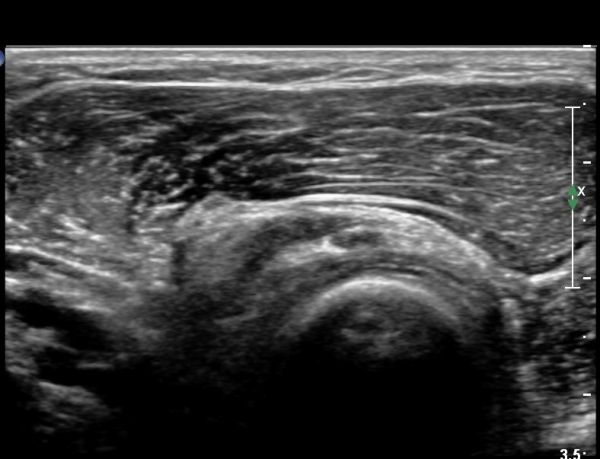

ŽÃËÀÚ¸¦ ¾à°£ ¸»´ÜÀ¸·Î À̵¿ÇÏ´Ï(¿ä°ñµÎ ºÎÀ§) Å« ³¶Á¾ÀÌ º¸ÀÌ°í ³¶Á¾ÀÇ ¿ÜÃø¿¡ Èİñ°£½Å°æÀÇ ¾Ð¹ÚÀÌ °üÂûµÈ´Ù(»çÁø 2). ³¶Á¾Àº ¿ä°ñµÎ¿¡¼­ ¿ä°ñºÎÀ§±îÁö À§Ä¡ÇØ ÀÖ´Ù(»çÁø 3)